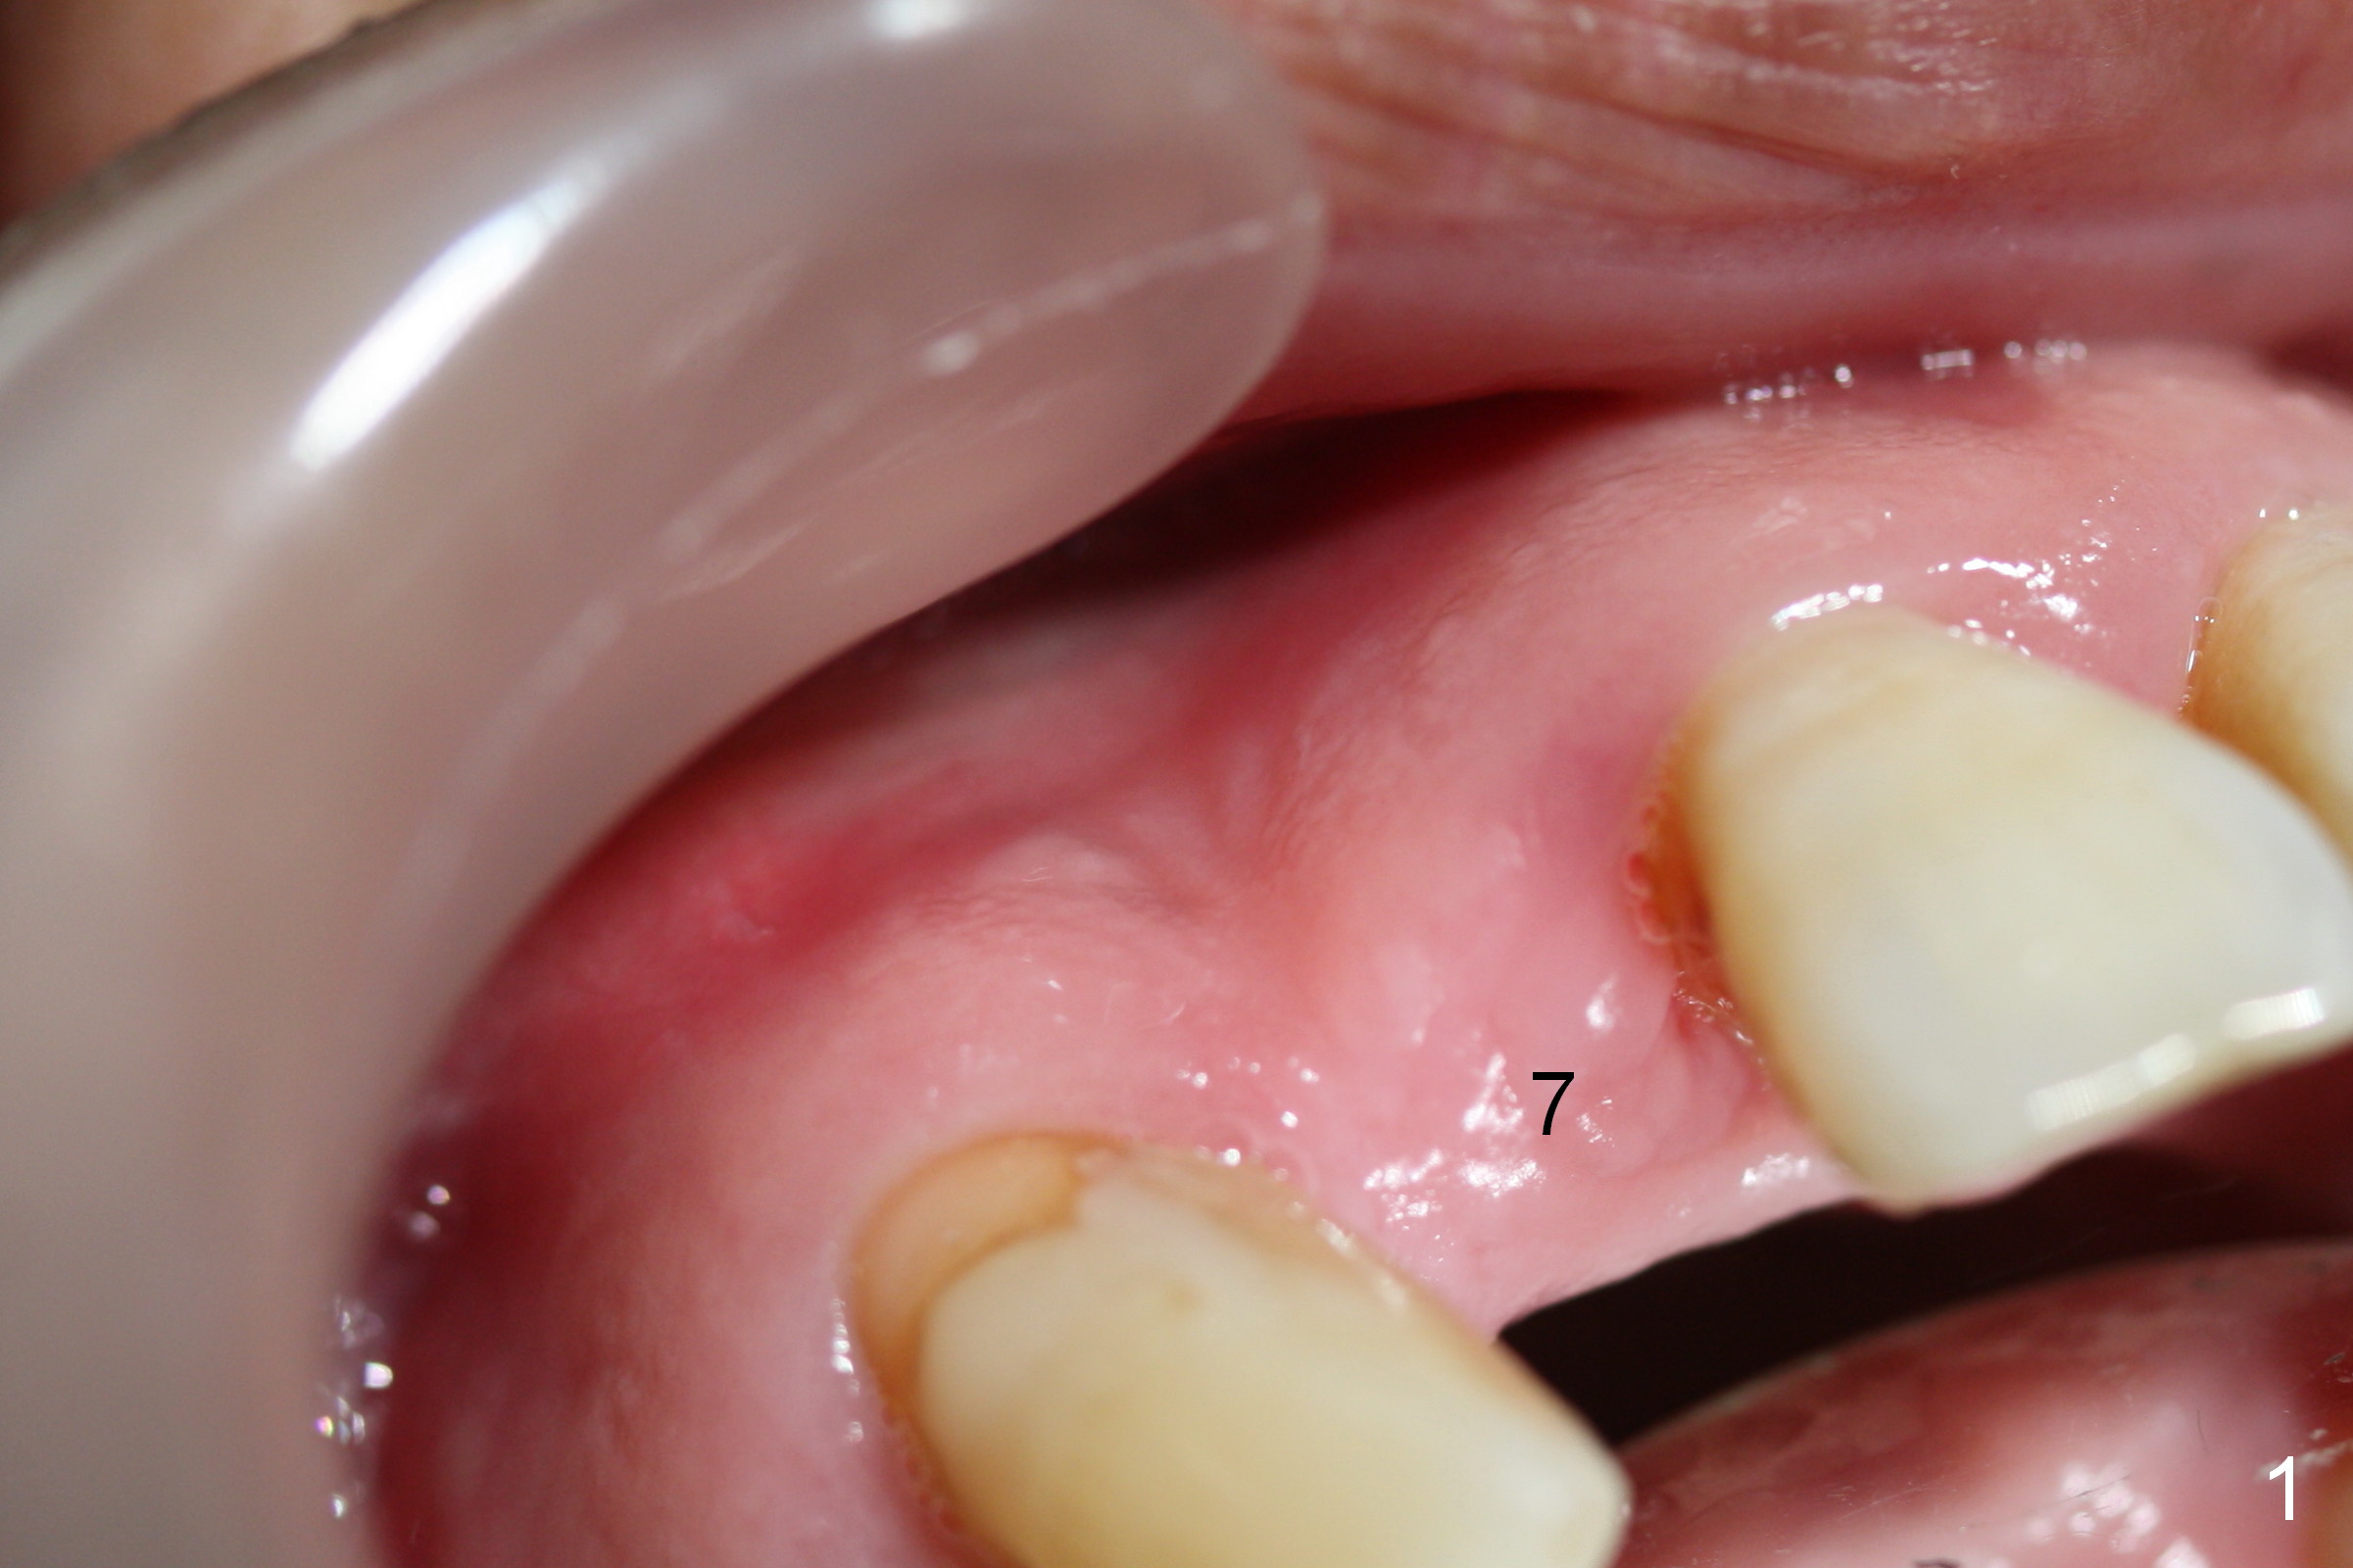

Preop exam shows the apparent wide ridge at #7 (Fig.1). What is ignored preop is the concavity in the apical buccal region (Fig.2 *). When a 3x16(4) mm 1-piece implant is being placed (Fig.3 *, flapless), the apical buccal plate vibration is felt. The biggest mistake is that initial osteotomy is ~ 6 mm shy of the implant length, partially because of 6 mm gingival height. Since the tooth #6 is symptomatic after RCT with paste overfill (Fig.4 >), apicoectomy is contemplated at #6 with exploration of the buccal plate at #7 (Fig.5). Since the implant appears to be long enough, implant apical resection is performed (Fig.6). Since there is coronal thread exposure due to previous periodontitis (Fig.7 <), bone graft is placed in these 3 defective areas after decortication.

Extending the initial osteotomy to the full length of the implant is critical. If perforation is detected early, the trajectory can be changed. Incision should be made if there is no CBCT study. The incision heals 1 and 4 weeks postop (Fig.8,9). The patient returns for final restoration 6 months postop. Apical defects appear to have healed at #6 and 7 (Fig.10,11). Fig.12 is taken 11 months postop and 5 months post cementation. The patient has an accident 9 months post cementation. In fact the implant is alright, while the tooth #6 fractures and #8 subluxates.